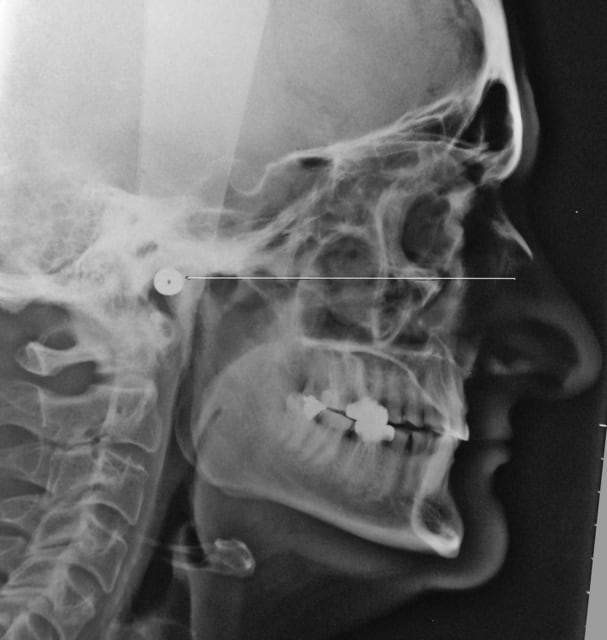

je vous mettrait les photos de la gouttière, mais là je me pose la question de l'augmentation de la DVO, à savoir de combien ?

si je regarde la téléradio de profil, ça me sort une augmentation énorme

si je regarde sa tronche, ça me dit d'augmenter beaucoup

si je regarde les rapports entre les antérieures, faut y aller un max

... bref, ça va me faire une augmentation d'1cm au niveau incisif je pense

4 determination de la DVO avec les critères suivants :

céphalométrie

proportions des dents

surplomb

recouvrement

esthétique du visage

hauteur prothétique antérieure et postérieure

au final j'aurais pu augmenter un peu plus pour être mieux devant, mais ça faisait une telle augmentation au niveau des prémos qui j'ai pas osé aller plus loin, et ça correspond tel quel aux valeurs de l'analyse cephalo